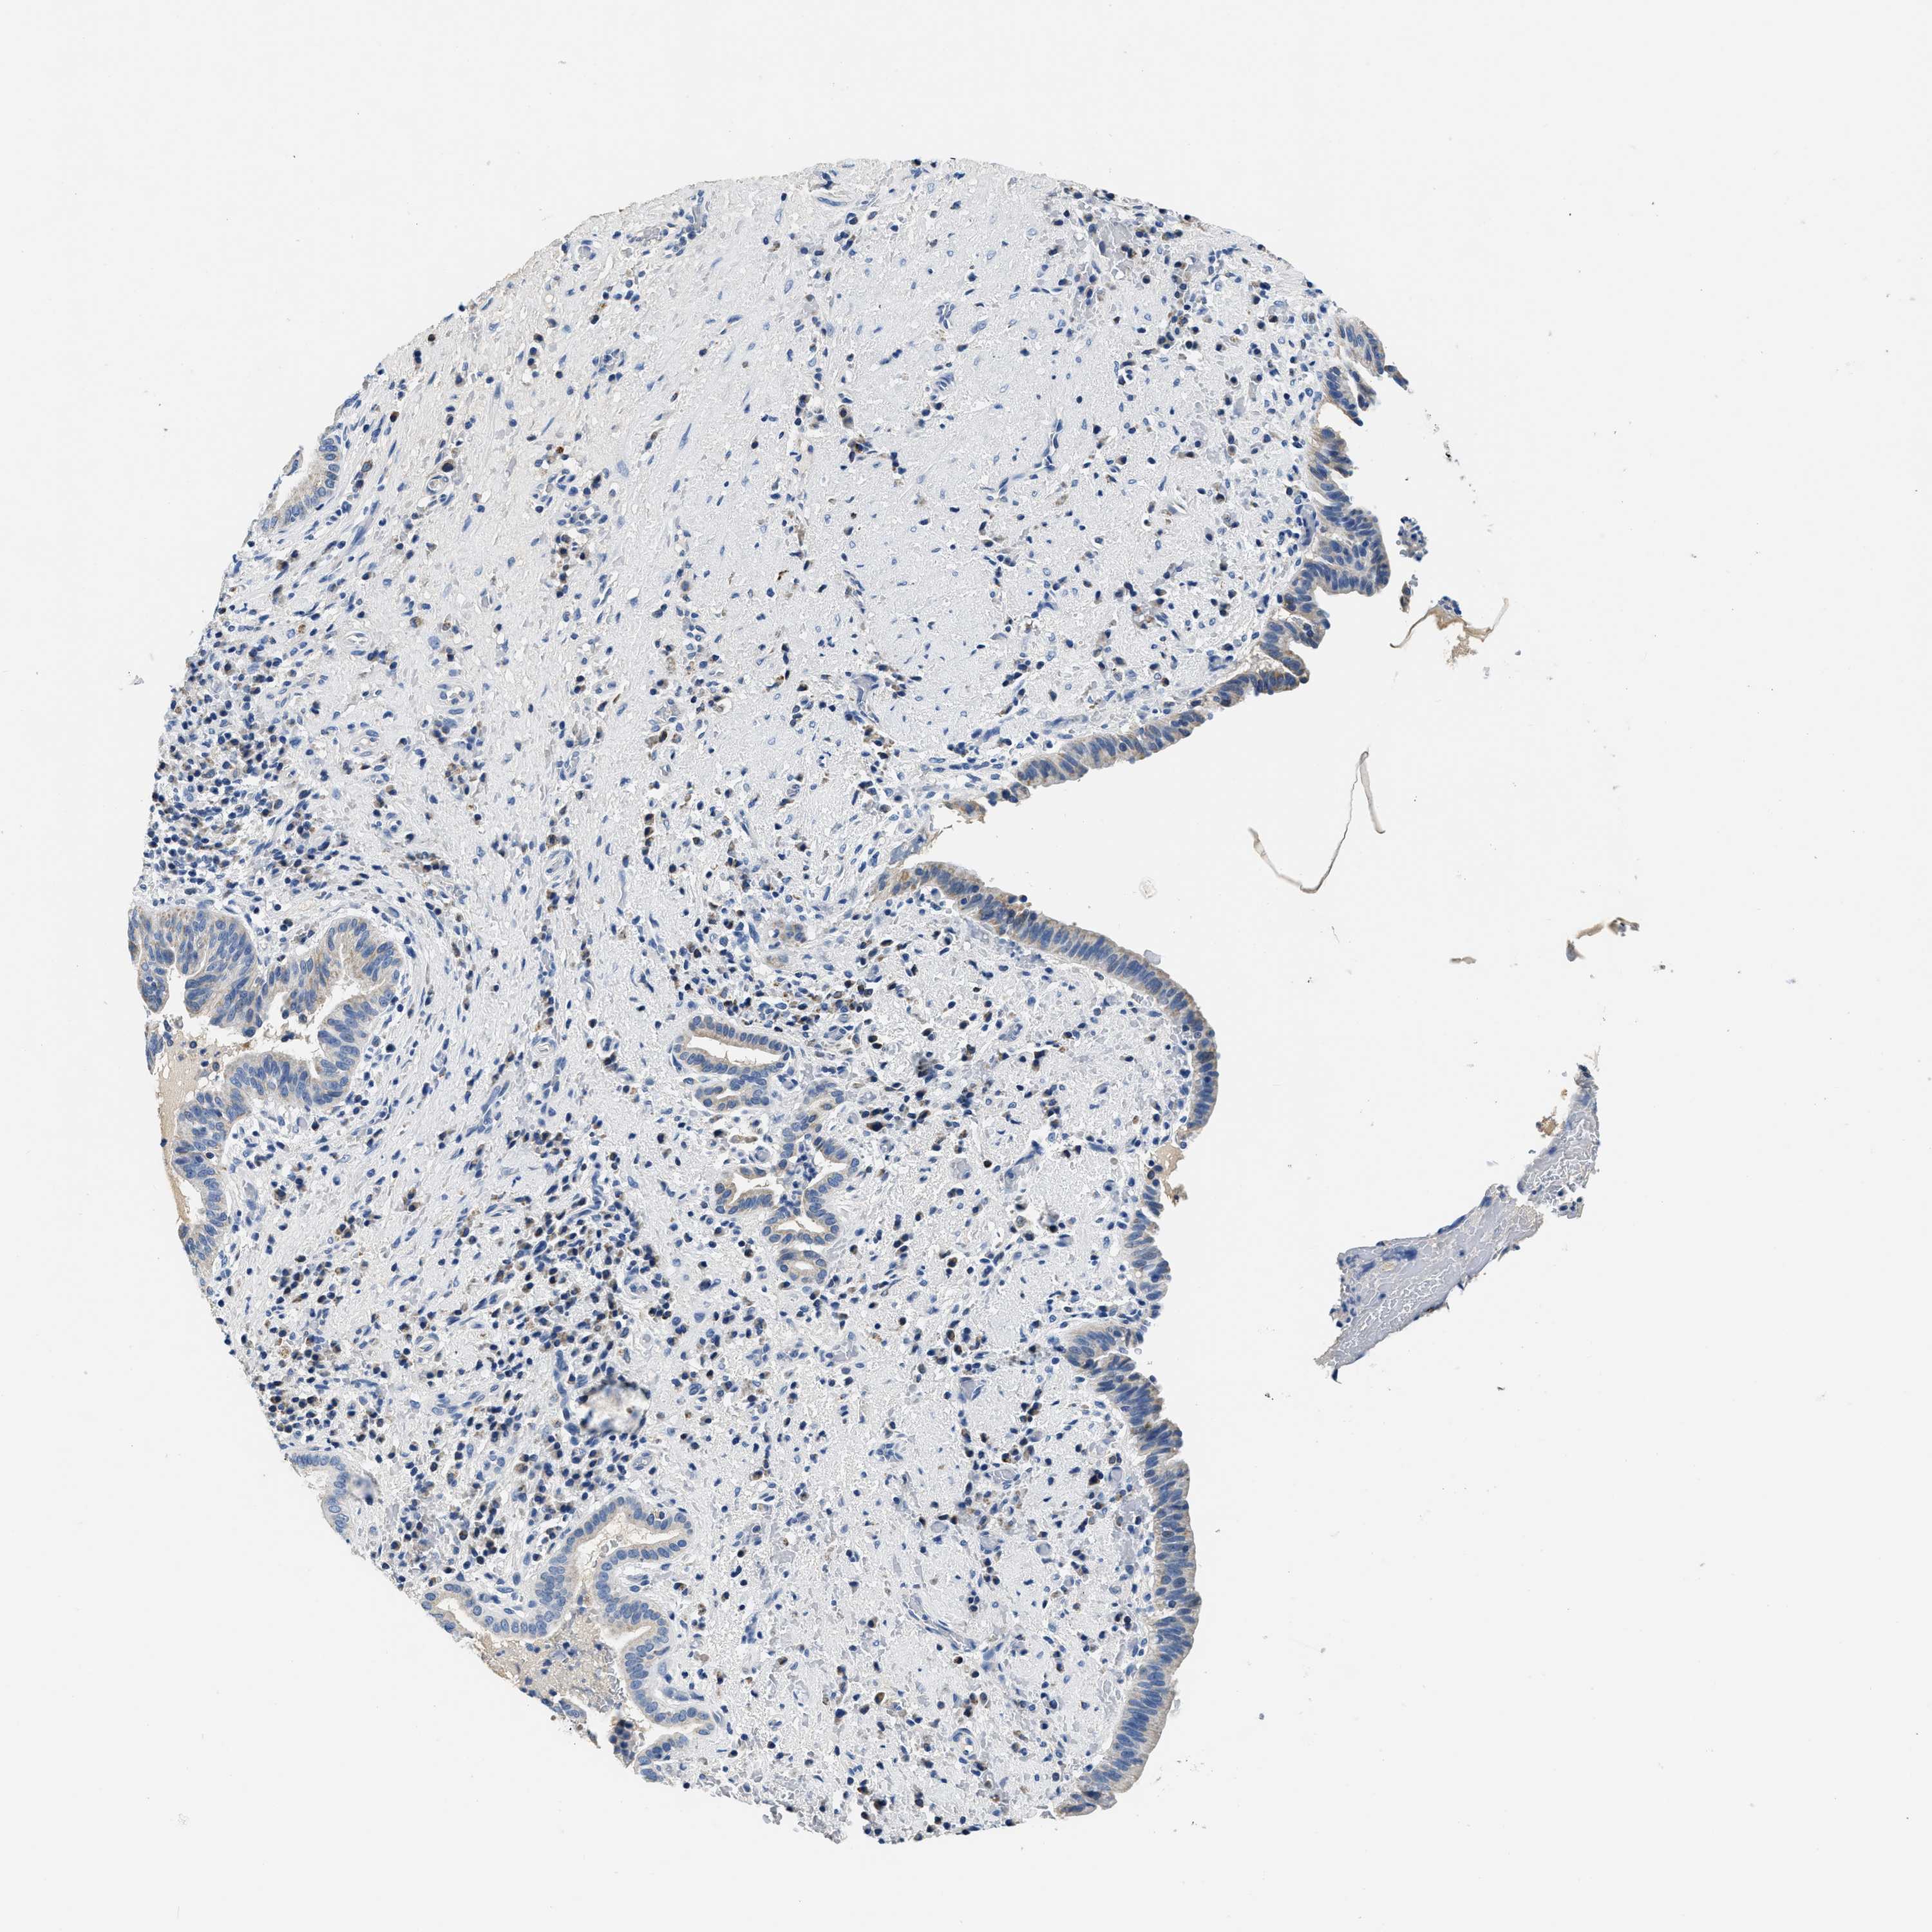

LIVER CANCER - Protein expressioni

A mouse-over function shows sample information and annotation data. Click on an image to view it in a full screen mode. Samples can be filtered based on level of antibody staining by selecting one or several of the following categories: high, medium, low and not detected. The assay and annotation is described here.

Note that samples used for immunohistochemistry by the Human Protein Atlas do not correspond to samples in the TCGA dataset.

Antibody stainingi

Antibody staining in the annotated cell types in the current human tissue is reported as not detected, low, medium, or high, based on conventional immunohistochemistry profiling in selected tissues. This score is based on the combination of the staining intensity and fraction of stained cells.

Each image is clickable and will lead to virtual microscopy that enables deeper exploration of all samples and also displays staining intensity scores, fraction scores and subcellular localization as well as patient and tissue information for each sample.

Antibody HPA051162

Antibody HPA053502

Antibody CAB018734

Staining

High

Medium

Low

Not detected

Intensity

Strong

Moderate

Weak

Negative

Quantity

>75%

75%-25%

<25%

None

Location

Nuclear

Cytoplasmic/membranous

Cytoplasmic/membranous,nuclear

Cholangiocarcinoma

Carcinoma, Hepatocellular, NOS